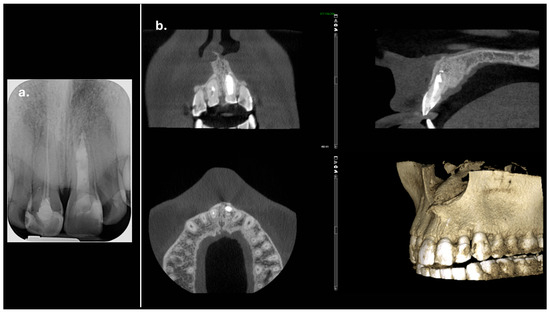

The periapical radiograph showed that tooth #21 had undergone previous endodontic treatment. A diffuse periapical radiolucency was observed surrounding the open apex. Additionally, the root appeared relatively short and exhibited thinner dentinal walls compared to the adjacent tooth #11 (Figure 1).

Figure 1.

Preoperative radiograph of tooth #21. The radiograph shows previous endodontic treatment, with the root canal filling material not extending to the full length of the canal. A diffuse radiolucency is visible around the open apex. (The mark in the lower left corner indicates the left side).

The CBCT scan revealed a labial cortical bone defect associated with tooth #21, measuring approximately 7 mm in diameter. The apical third of the root was uncovered by bone; an apical bone fenestration was present. The palatal cortical bone remained intact and was not affected by the periapical pathology (Figure 3). According to the CBCT Periapical Index (CBCTPAI), the lesion was classified as score 4 + D, indicating extensive periapical radiolucency with destruction of the cortical bone [9].

Figure 3.

The labial bone fenestration is visible on the CBCT image (indicated by red arrows).